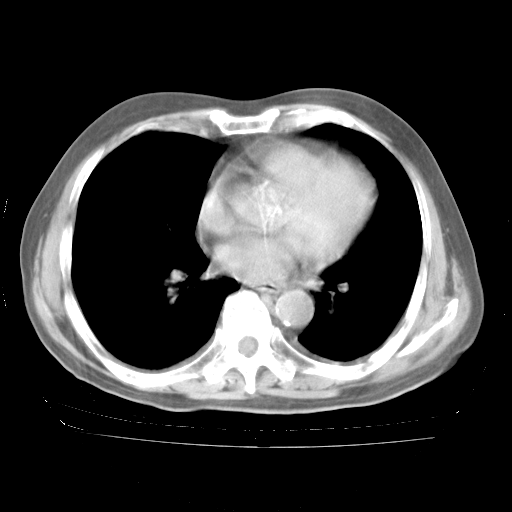

4月28日肺部CT——再次出现类似去年5月9日——透光度降低,“间质性”改变。

4月28日肺部CT——再次出现类似去年5月9日——磨玻璃样、间有“粟粒样”改变。

4月28日肺部CT

个人阅读4.14日肺部CT平扫:纵隔窗无异常,但肺窗示:双下肺内、后基底段有片絮状侵润影,部位以后基底段为著,以间质改变为主,呈急性肺泡炎征像,和首次住院影像学有相似之处。仅是个人读片,明日请相关专家再读片哈。其它建议同上。

1、108#的是4月14日的胸部CT(发此贴时还没看着28日的CT)。14日的胸部CT其实已经出现改变(如108#所述),个人认为28日的胸部CT除纵膈窗疑似有双侧胸膜增厚或少量胸积液(可行胸部B超明确)外,与4月14日对照病变有所加重;2、已经给予“异烟肼、利福平、乙胺丁醇”抗痨治疗?如果是,甲强龙80mg可缓慢减量;如果环磷酰胺已停用,暂不使用;3、中性粒细胞92%,明显升高,目前体温情况?注意合并细菌感染可能,使用左氧氟沙星情况下,是否联用B-内酰胺类抗菌药物?另外是查免疫全套非风湿全套。

今请临免主任会诊后认为:4月14日胸部CT已有双下肺间质性改变。患者病情复发多系激素减量过快不正规所致。目前甲强龙80mg/日,一周后酌情开始减量,不易过快。环磷酰胺若已停用,暂不使用。他同意目前抗菌药物使用,但应考虑是否加用B-内酰胺类抗菌药物(中性细胞明显增高);2、结核复发目前依据不足;3、若免疫全套各项指标正常,考虑多系特发性肺间质炎可能大。4、加强支持,并注意保护胃黏膜。